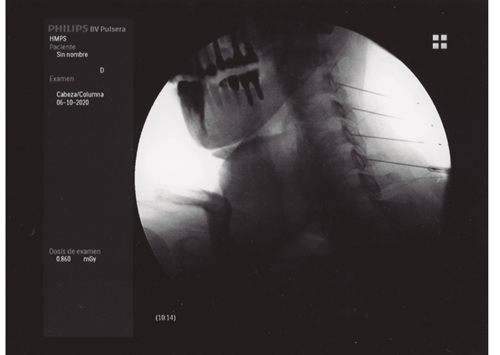

Figura 3